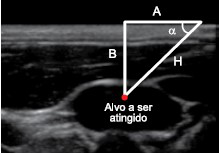

Na prática diária da medicina, a trigonometria pode ser utilizada para determinar, por exemplo, a inclinação que devemos dar a uma agulha com o objetivo de atingir o local desejado. A imagem indica a anatomia ultrassônica da veia jugular interna de um paciente. Nessa imagem, H representa a medida do trajeto retilíneo da agulha que incidirá na pele do paciente, A representa a distância, medida na pele retilínea do paciente, entre o ponto de incisão da agulha e o ponto correspondente à projeção ortogonal do alvo a ser atingido sobre a pele, e B representa uma medida que depende da anatomia de cada paciente.

Seja (A, !$ α !$) um par ordenado, com A em centímetros e !$ α !$ em radianos. Suponha que a imagem de ultrassom apresentada indique ao médico B = 2 cm e cinco pares (A, !$ α !$), dados por

S1 = !$ \begin{pmatrix}2 \sqrt{3},\dfrac{π}{3} \end{pmatrix} !$, S2 = !$ \begin{pmatrix}3\sqrt{3},\dfrac{π}{6} \end{pmatrix} !$, S3 = !$ \begin{pmatrix}2, \dfrac{π}{4} \end{pmatrix} !$, S4 = !$ \begin{pmatrix}\dfrac{2 \sqrt{3}}{3},\dfrac{π}{6} \end{pmatrix} !$ e S5 = !$ \begin{pmatrix}1,\dfrac{π}{4} \end{pmatrix} !$ será atingido corretamente.

Nessas condições, dentre os cinco pares (A, !$ α !$), aquele que atingirá corretamente o alvo será